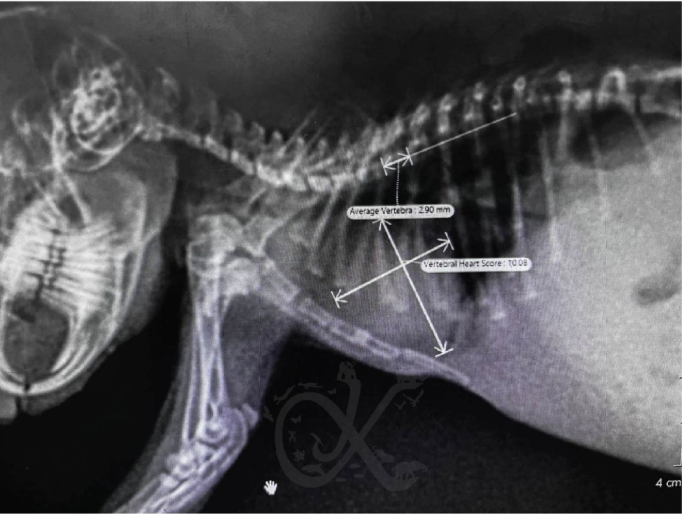

Vertebral Heart Score (VHS): This is a standardized measurement where the length and width of the heart are compared against the length of the rabbit’s thoracic vertebrae (spine). If the heart exceeds a certain number of vertebral units, it indicates cardiomegaly.

Tracheal Elevation: An enlarged heart often pushes the trachea (windpipe) upward toward the spine, which is visible on a lateral (side view) X-ray.

Cardiac Silhouette: Vets assess the overall shape and size of the heart "shadow" to see if specific chambers (like the left atrium) are bulging.